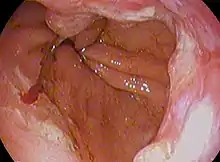

| Endoscopic image of an esophageal adenocarcinoma | |

Although an occlusive tumor may be suspected on a barium swallow or barium meal, the diagnosis is best made with an examination using an endoscope. This involves the passing of a flexible tube with a light and camera down the esophagus and examining the wall, and is called an esophagogastroduodenoscopy. Biopsies taken of suspicious lesions are then examined histologically for signs of malignancy.

Endoscopic image of Barrett esophagus – a frequent precursor of esophageal adenocarcinoma